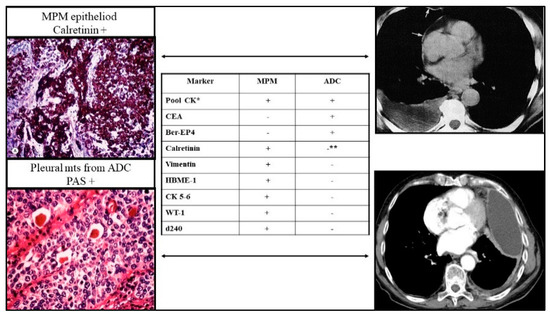

- Bianco, A.; Valente, T.; De Rimini, M.L.; Sica, G.; Fiorelli, A. Clinical diagnosis of malignant pleural mesothelioma. J. Thorac. Dis. 2018, 10 (Suppl. 2), S253–S261. [Google Scholar] [CrossRef]

- Stella, G.M.; Senetta, R.; Cassenti, A.; Ronco, M.; Cassoni, P. Cancers of unknown primary origin: Current perspectives and future therapeutic strategies. J. Transl. Med. 2012, 10, 12. [Google Scholar] [CrossRef]